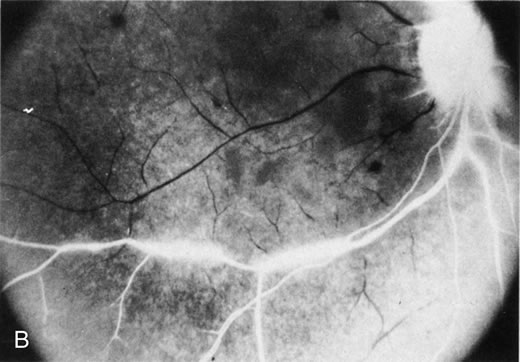

The finding of retinal vascular changes in patients with SLE correlates with the activity of the disease.214 The relationship of cotton-wool spots alone to CNS lupus has been debated, but to date no relationship has been established. Most experts feel that the finding of cotton-wool spots does not indicate the presence of CNS lupus. A much less frequent, severe retinal vasoocclusive disease has been described and does appear to be associated with CNS lupus, in particular, diffuse CNS dysfunction, such as an organic brain syndrome.214–223 This more severe retinal vasoocclusive disease may present as a central retinal artery occlusion, central retinal vein occlusion, branch artery occlusion, or most frequently, a diffuse retinal vasoocclusive process (Fig. 5), sometimes called retinal vasculitis. Although this last process sometimes has been called retinal vasculitis, the exact pathogenesis may not be true vasculitis. Cases of severe retinal vasoocclusive disease in SLE in association with the lupus anticoagulant also have been reported, and the retinal disease in these cases is presumed to be secondary to this autoantibody (Fig. 6).190,191 The prognosis for vision with this diffuse retinal vascular disease is poor and retinal neovascularization commonly develops. Panretinal photocoagulation may be of value in the treatment of the neovascularization of severe lupus retinopathy. Approximately 50% of eyes affected with this severe vaso-occlusive disease become blind. Although visual loss is common in those patients with severe retinal disease, in the more common mild retinopathy visual loss is unusual.223

Fig. 5. A. Fundus photograph and B. fluorescein angiogram, demonstrating diffuse vaso-occlusive disease in a patient with systemic lupus erythematosus. Fluorescein angiogram shows extensive nonperfusion of the retina. (Jabs DA, Fine SL, Hochberg MC, et al: Severe retinal vaso-occlusive disease in systemic lupus erythematosus. Arch Ophthalmol 1104:558, 1986. Copyrighted 1986, American Medical Association. Reprinted with permission.)